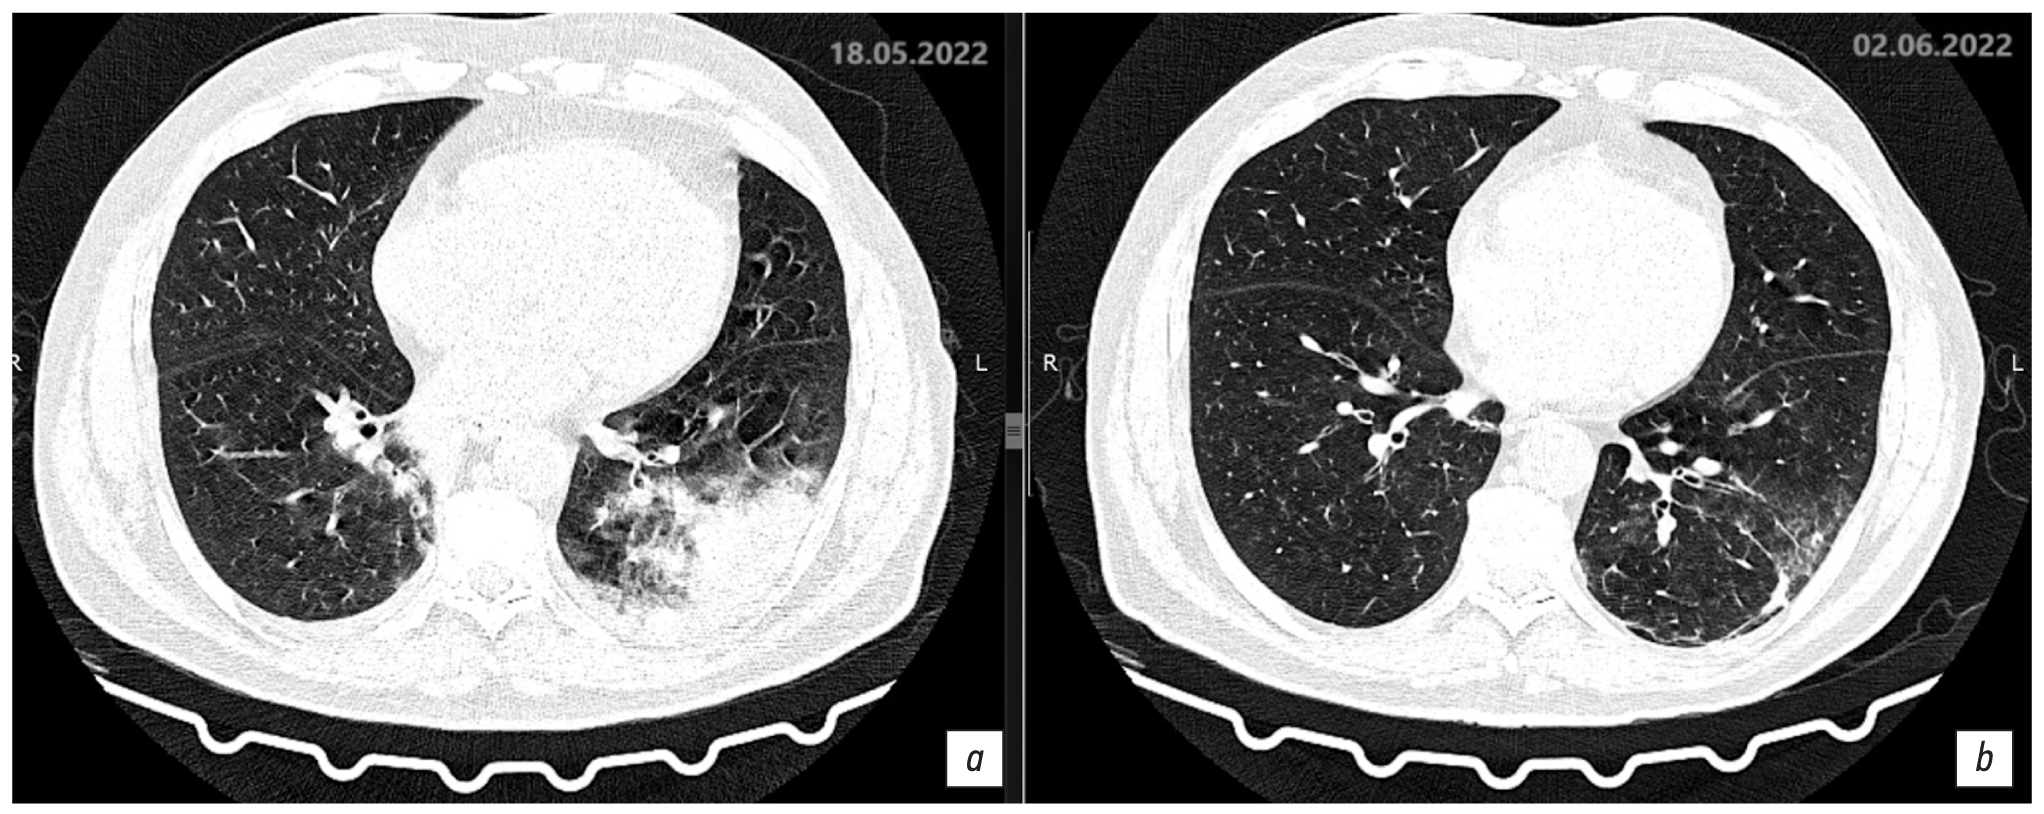

Description of the chest CT scan dated May 18, 2022, day 8 of the disease, day 3 of hospitalization (Fig. 7a, 8a). The lungs display negative infiltrative changes, with increasing extent and size, and new infiltration areas occurred in the lower lobe of the right lung. The lungs are fully expanded. Multiple segments of the lungs exhibit extensive confluent areas of heterogeneous infiltration of the consolidation type with a peripheral rim of ground glass are observed, with visible bronchial lumen. Focal masses with somewhat radial contours, measuring up to 3.8 × 5.1 mm and 7.9 × 6.2 mm, are observed in the upper S2 segment on the right side. The bronchial lumen is patent, and the intrathoracic or axillary lymph nodes are not enlarged. Free fluid in the pleural cavities is observed on both sides. On the right side, the fluid extends up to 7–8 mm (previously 5–6 mm), whereas on the left side, the fluid reaches up to 6 mm (previously 2–4 mm). The heart is unremarkable. Results: CT pattern of negative changes in bilateral multifocal pneumonia and bacterial disease (legionellosis?). Focal lesions in the right lung without changes and minor bilateral hydrothorax with slightly negative changes.

Fig. 7. Axial sections showing changes at the level of the upper parts of the lungs over time, pulmonary window: a: chest CT scan dated May 18, 2022, day 8 of the disease, day 3 of hospitalization; b: chest CT scan dated June 2, 2022, day 23 of the disease, day 17 of hospitalization.

Fig. 8. Axial sections showing changes at the level of the lower parts of the lungs over time, pulmonary window: a: chest CT scan dated May 18, 2022, day 8 of the disease, day 3 of hospitalization; b: chest CT scan dated June 2, 2022, day 23 of the disease, day 17 of hospitalization.

The therapy was adjusted to add intravenous azithromycin 500 mg daily. Levofloxacin and azithromycin were continued for a period of 14 days. Gradual improvement was observed. On day 17 of the disease, May 28, 2022, the patient’s condition was of moderate severity, the improvement was due to decreased respiratory failure symptoms. Blood chemistry results improved: CRP 6.0 mg/L, urea 4.7 mmol/L creatinine 89 μmol/L, WBC 6.5 × 109/L, and lymphocytes 3.8 × 109/L.

Description of the chest CT scan dated June 2, 2022, day 23 of the disease, day 17 of hospitalization (Fig. 7b, 8b). Compared to the previous CT scan on May 18, 2022, there is a notable improvement in the extent, size, and intensity of infiltration in the lungs. The lungs are fully expanded. Multiple segments of the lungs show rare confluent areas of heterogeneous infiltration, characterized by heavy consolidation and ground glass appearance. Focal masses with somewhat radial contours, measuring up to 3.8 × 5.1 mm and 7.9 × 6.2 mm, are observed in the upper S2 segment on the right side. The bronchial lumen is patent, and the intrathoracic or axillary lymph nodes are not enlarged. Free fluid in the pleural cavities on both sides remains undetermined (previously noted on the right up to 7–8 mm, on the left up to 6 mm). The heart is unremarkable.

Results: CT pattern of positive changes of bilateral multifocal pneumonia (stage of incomplete resolution). Focal lesions in the right lung. Follow-up is recommended. Minor bilateral hydrothorax shows positive changes.

Description of the chest CT scan dated May 15, 2022, on day 5 of the disease, day 1 of hospitalization. The lungs are fully expanded. In S2 of the right lung (subtotally with marked reticular changes) and in S1/2 and S6 segments of the left lung, subpleural confluent areas of heterogeneous infiltration of consolidation type with a peripheral rim of ground glass are observed, with bronchial lumen visible in the affected S2 segment of the right lung. Focal masses with somewhat radial contours, measuring up to 3.8 × 5.1 mm and 7.9 × 6.2 mm, are observed in the upper S2 segment on the right side. Degrees of pathological changes in each lobe are as follows: right lung: upper lobe 35%, middle lobe 0%, lower lobe 0%; left lung: upper lobe 10%; lower lobe 15%–20%. The total lesion is approximately 20%. The bronchial lumen is patent, and the intrathoracic or axillary lymph nodes are not enlarged. There are minimal amounts of free fluid in the pleural cavities on both sides, with the largest quantity observed on the right side at 5–6 mm and on the left side at 2–4 mm. The heart is unremarkable. Results: CT pattern of bilateral multifocal pneumonia with intermediate probability of viral etiology (CT1, approximately 20%). Focal masses in the right lung warrants a follow-up examination. Minor bilateral hydrothorax.

On May 18, 2022, day 3 of hospitalization, negative changes were observed due to increasing intoxication and respiratory syndromes, as well as onset of respiratory failure (oxygen saturation: 90%, RR: 22 per minute). Humidified insufflation with a flow rate of 6 L/min was connected, resulting in saturation of 95%. Clinical diagnosis: Legionellosis (severe course), bilateral multifocal pneumonia (severe), respiratory failure (grade 1). Follow-up chest CT was performed.